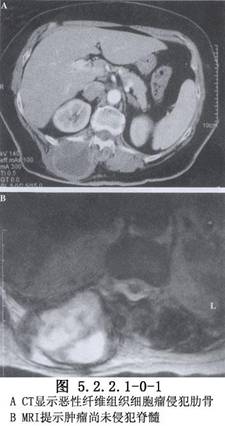

除病史及體格檢查外,還要攝胸部X線片,斷層攝影等必要的檢查。胸壁軟組織腫瘤X線片的特點爲陰影密度不高。切線位片瘤體中心位於側胸壁,瘤體與胸壁成鈍角。骨良性腫瘤一般爲圓形、橢圓形,骨皮質無斷裂。骨軟骨瘤常見在肋骨骨髓區內,頂部呈圓形或菜花狀,境界銳利,有不規則鈣化軟骨帽,瘤內有點狀鈣化。軟骨瘤常發生在肋骨與肋軟骨交界處,腫瘤有分葉,受累骨膨脹,骨皮質變薄,內有點狀鈣化,難與軟骨肉瘤鑑別。骨纖維結構不良,常發生在後側肋骨,始自嬰幼兒期,常到青壯年才發現,病竈呈侷限性膨大,骨皮質變薄,病變區呈磨玻璃樣變。肋骨骨鉅細胞瘤有皁泡狀透亮區,骨皮質薄如蛋殼。惡性腫瘤X線所見,主要爲侵蝕性骨破壞,呈篩孔樣、蟲蝕樣,可見溶骨或成骨性改變,邊緣較毛糙,骨皮質缺損、中斷或病理性骨折。軟骨肉瘤起自骨髓部分,呈分葉狀腫塊,邊緣不清,內有點狀或斑狀鈣化竈。骨肉瘤X線表現分爲溶骨型、成骨型及混合型3種。成骨型有放射狀排列的新生針狀骨小梁,邊界不清。Ewing肉瘤佔原發性胸壁骨腫瘤的12%,X線片見骨呈斑片狀破壞,含有溶骨和增生區,骨膜增生呈層狀,稱“蔥皮”樣改變。MRI可將腫瘤與血管區別,應採用不同平面瞭解腫瘤情況。活檢是診斷的可靠方法,應注意惡性腫瘤常有良性部分,多部位、足夠組織取材是正確診斷的關鍵。胸壁腫瘤的診斷十分重要,它決定治療方法的選擇(圖5.2.2.1-0-1~5.2.2.1-0-5)。